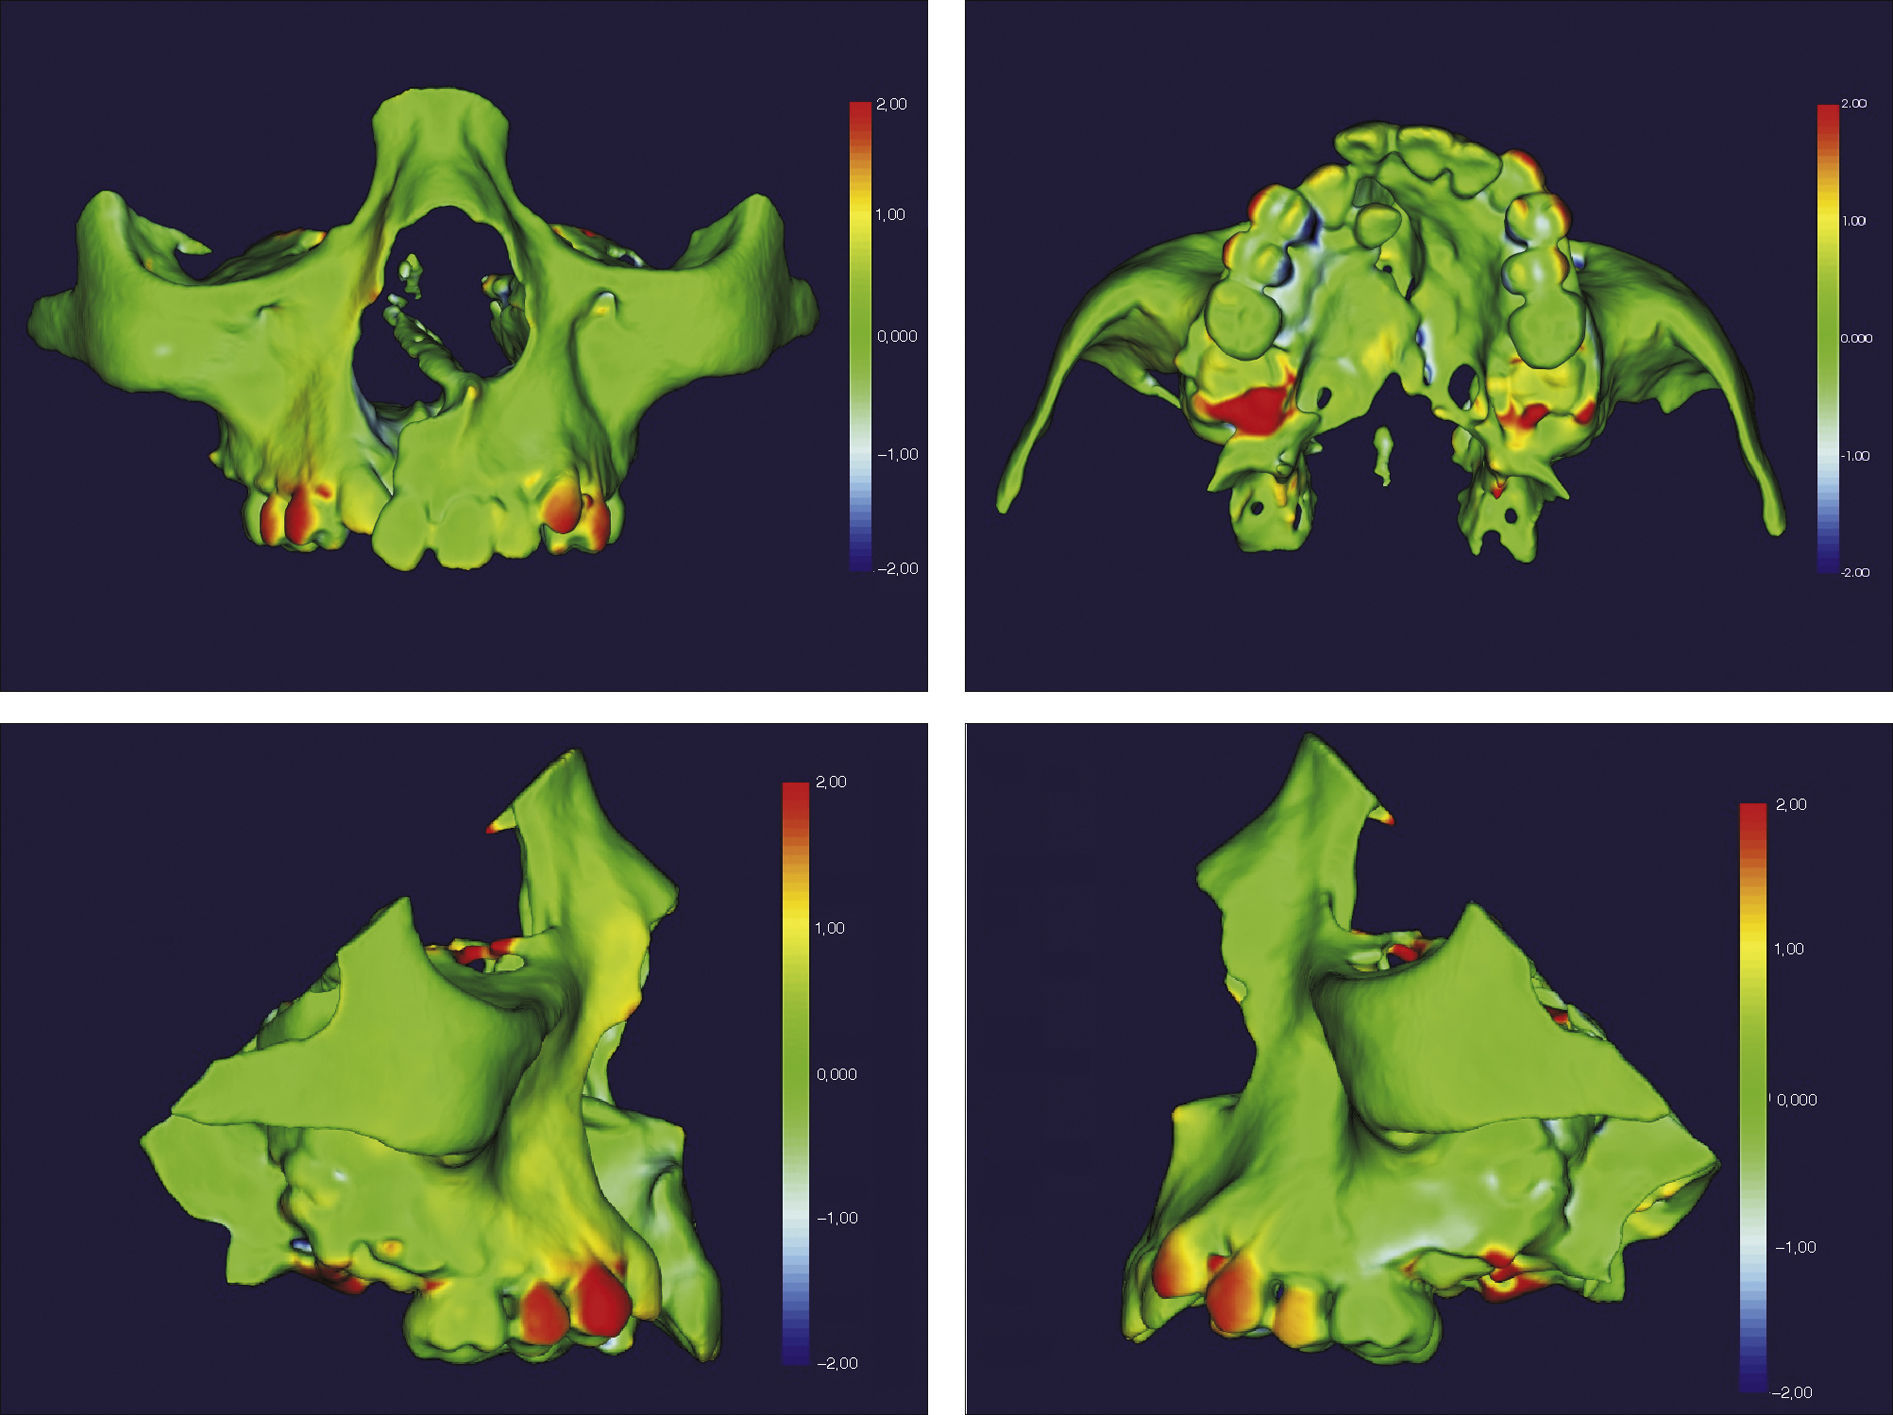

O surgimento e o aumento da acessibilidade da TCFC agregaram uma maior credibilidade ao diagnóstico clínico e às investigações científicas no estudo das deformidades craniofaciais19. Todavia, as informações 3D fornecidas pelas TCFC ainda vêm sendo rotineiramente analisadas de forma 2D, por medidas lineares em cortes ortogonais5,20. A construção e sobreposição de modelos virtuais 3D ainda é uma metodologia pouco difundida. Este estudo é um dos pioneiros que utiliza este método para avaliação de ERM em pacientes com fenda. A sobreposição baseia‐se na construção dos modelos virtuais 3D, utilizando o software SLICER21, pelos arquivos obtidos na TCFC, seguida pela sua justaposição, que utiliza a base do crânio como referência e a final obtenção dos métodos de medidas intitulados: sobreposição por semitransparência e mapa por códigos de cores22. A sobreposição por semitransparência revela uma análise qualitativa, em que o momento pós‐tratamento é retratado por uma malha preta translúcida, sobre o modelo inicial em vermelho (figs. 9 e 10). O aparelho em leque demonstrou um deslocamento de quase todos os dentes para vestibular e uma movimentação vestíbulo‐posterior do segmento menor (lado esquerdo [fig. 9]). O mapa por códigos de cores permite um complemento da análise visual, sendo que cada cor reflete uma alteração na posição das estruturas: azul – recuo; verde – estabilidade e vermelho – expansão. A intensidade da cor está diretamente relacionada à quantidade de movimentação. Todo o mapa é seguido por uma escala, com os valores em milímetros para cada cor (figs. 11 e 12). A observação feita na sobreposição por semitransparência do expansor em leque é confirmada no mapa por código de cores e nas medidas lineares. Uma menor porção de vermelho é visualizada em molares, quando comparada aos pré‐molares. O deslocamento para posterior e vestibular do menor segmento é constatado pela presença de azul na mesial dos dentes e vermelho nas eminências alveolares do lado em questão. Diferentes tonalidades de azul são vistas na cervical dos incisivos, possivelmente uma retroinclinação em decorrência da ausência de apoio mecânico no local. Para a quantificação das mudanças no posicionamento dentário, primeiramente identificou‐se, nos 3 cortes ortogonais, os pontos de referência para a medida (ponta da cúspide mésio vestibular dos primeiros molares superiores e ponta da cúspide dos caninos), tanto do lado direito como do lado esquerdo, utilizando o software ITK Snap23. Os pontos foram marcados com uma esfera de 0,5mm de diâmetro, identificando a posição 3D destas referências no espaço (fig. 13). A aferição das distâncias Euclidianas entre as esferas foi realizada com o auxílio da ferramenta Q3DC no programa SLICER23. O paciente A obteve um aumento de 3mm na distância intercanina e de 6mm na distância intermolar. Na elucidação do paciente que utilizou o disjuntor mini‐Hyrax invertido com BTP (B), observa‐se na sobreposição por semitransparência um deslocamento vestibular, principalmente dos pré‐molares e uma constância das demais áreas, achados corroborados no mapa por código de cores. A área que não está verde é a região de pré‐molares, vermelho por vestibular e azul por palatino, notando uma tonalidade entre verde e vermelho (amarelo) no corpo da maxila do lado menor (esquerdo). A oclusal dos molares, em vermelho, representa a erupção dos elementos.

Sobreposição com semitransparência dos modelos 3D do tratamento com o aparelho em leque. Antes da expansão representado por vermelho e após a expansão pela malha fina translúcida. Observa‐se um trespasse da malha preta para vestibular em molares, pré‐molares e canino, indicando que houve expansão em toda essa região.

Sobreposição com semitransparência dos modelos 3D do tratamento com o aparelho mini‐Hyrax invertido com BTP. Antes da expansão representado por vermelho e após a expansão pela malha fina translúcida. Observa‐se um trespasse da malha preta para vestibular na região dos pré‐molares, indicando expansão concentrada nessa região.